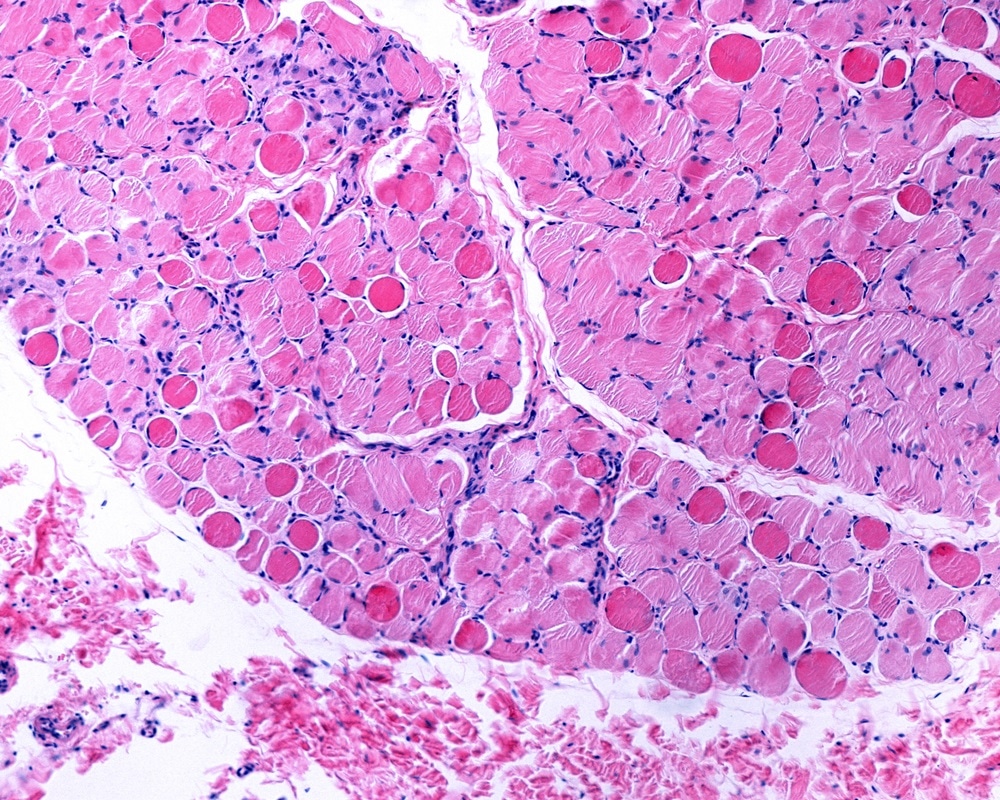

Duchenne muscular dystrophyImage Credits: Jose Luis Calvo / Shutterstock.com

Duchenne muscular dystrophy (DMD) is an X-linked genetic disorder that causes changes in the protein dystrophin, which maintains the integrity of muscle cells. This leads to muscle degeneration, chronic inflammation, weakness and a poor ability to regenerate any muscle tissue that has been lost.